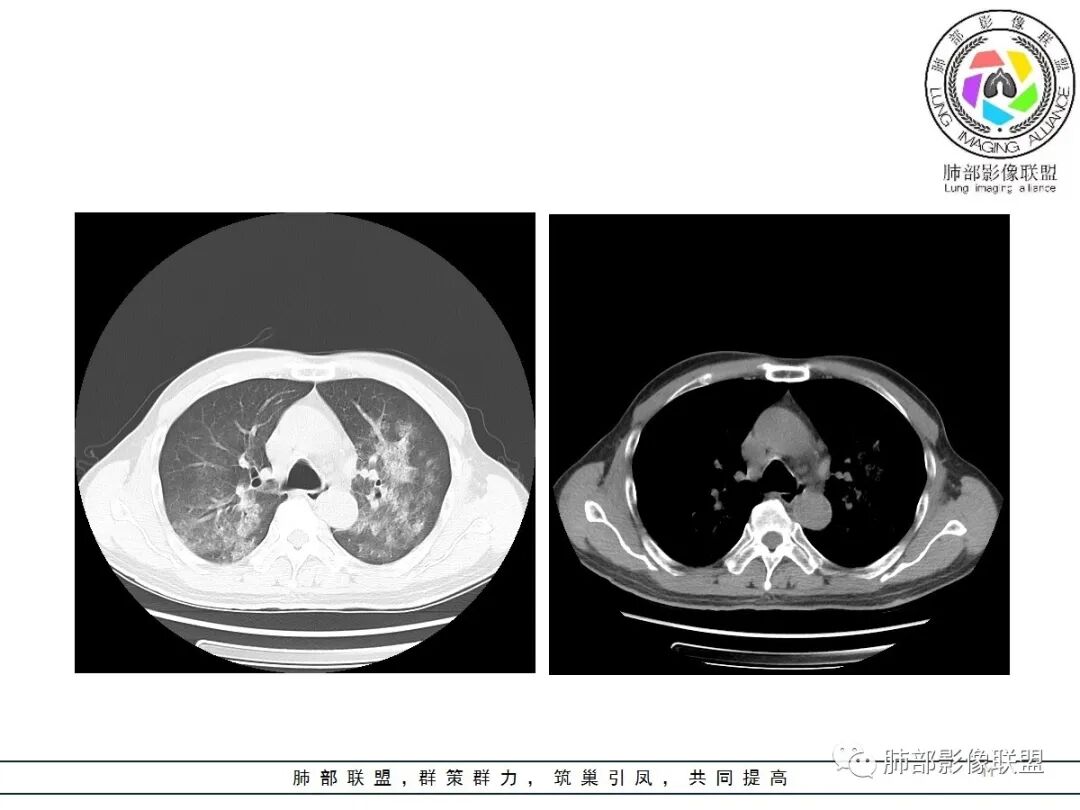

影像:双肺对称性中内带为主分布磨玻璃影,实变不明显。无胸水及小叶间隔增厚。

老年男性,咳嗽发热38度1天,crp、血象增高,pct不高,血气尚可,饲鹦鹉。双肺弥漫中心性多发磨玻璃密度影,以肺门区为中心性GGO伴细网格,无小叶间隔增厚,考虑非典,鹦鹉热?鉴别DAH

男,65,咳嗽、发热1天,黄粘痰,痰中带血。饲养鹦鹉,新冠疫苗第二针后,本地有新冠病例。血像高。胸部CT:双肺中内带多发斑片样磨玻璃影,边缘不清,沿支气管血管束分布,左肺重,细网络,小叶内间隔增厚,支气管充气征。诊断:肺门为中心两侧大概对称GGO,首先考虑DAH(血管炎)?不典型病原体感染,鹦鹉热、病毒待排。鉴别肺水肿、PCP等。

1.间质性肺水肿:小叶间隔增厚,尚光滑,支气管血管束增粗,肺血管影模糊,胸膜或叶间裂增厚,肺内有磨玻璃密度影,常有重力分布趋势。

2.肺泡性肺水肿 :

(1)中央型分布:以肺门为中心,两肺中内带对称分布的大片状实变,称为“蝶翼征”。常见于心源性及肾源性肺水肿患者。也可表现为磨玻璃密度病灶,弥漫性分布或以小叶中心性分布。

(2)弥漫型肺水肿:弥漫分布于两肺内的多发斑片状磨玻璃密度及实变影,大小和密度不等,可融合成大片状阴影,可见空气支气管征。